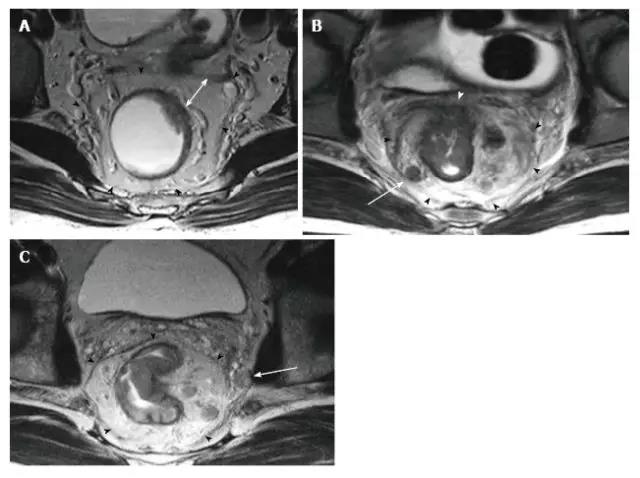

图 13. EMVI。T2 加权(A)冠状和(B 和 C)连续轴向磁共振图像,在 T4a 直肠癌患者中显示不规则和扩大的血管信号插入肿瘤,与肿瘤有相同的信号强度(圆圈)。